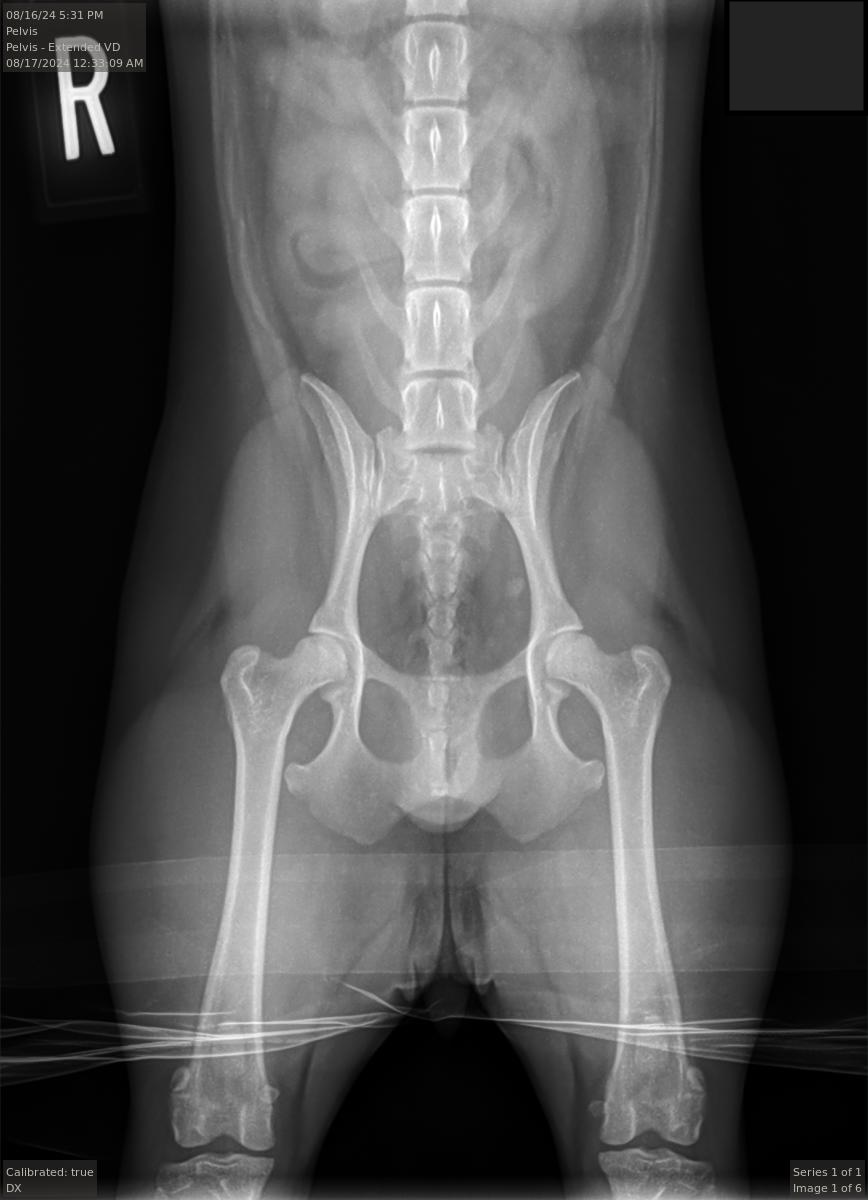

ofa | pelvis

rating | good

pennhip

right di 0.41 | left di 0.34